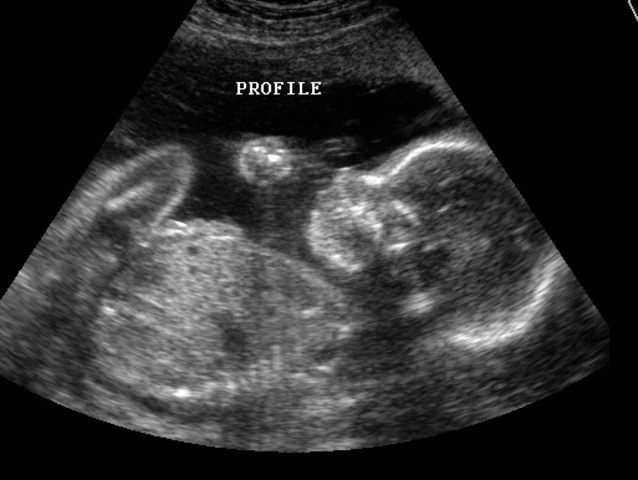

• Invention of the first ultrasound

Invention of the first ultrasound

In 1957 an English physician, Ian Donald, invented the first ultra sound. Ultra sounds cna be used to see babies, view the heart or look at the stomach. Essentially they can be used to view a lot of internal stuff.